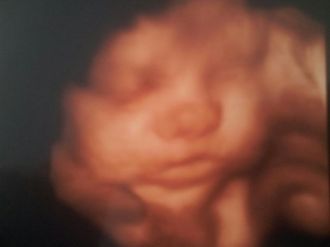

Petite séance echo ce matin....

nous avons eu un début diffcile le petit etait tourné et avait décidé de dormir apres avoir fait bouger le bebe, la maman ect ...derniere option marcher en sautillant lol...

et victoire nous avons eu de belles images du petit ....